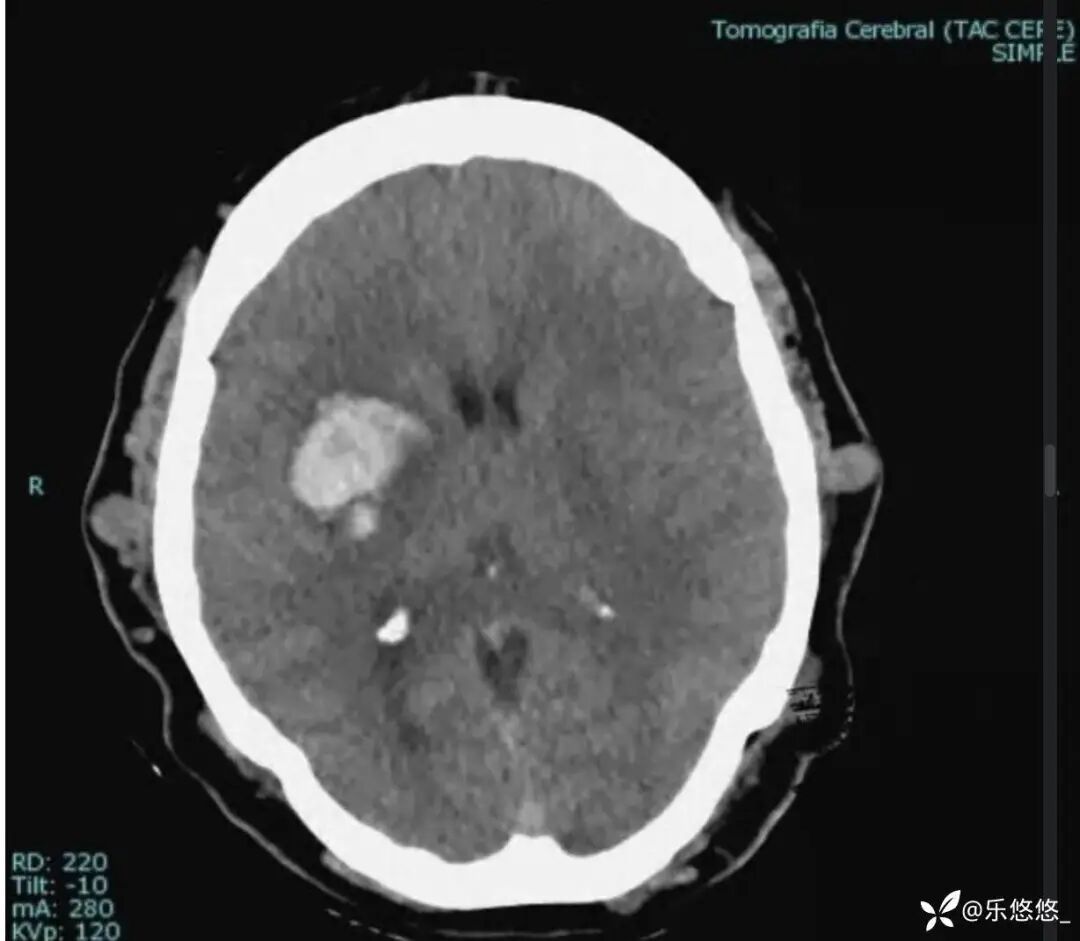

患者信息:45 岁女性,因「意识丧失,口角歪斜」入院。既往有高血压病史。

头部 CT 平扫显示右侧基底节区脑实质内出血,大小为 4.2x2.6cm,压迫右侧侧脑室。头皮不规则,可见多发类圆形和管状病变。